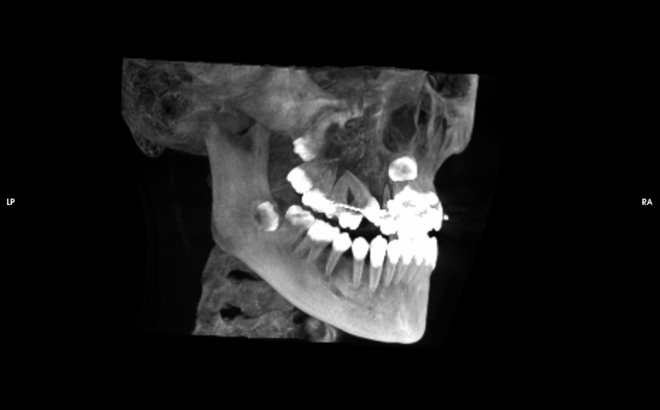

歯や骨を3次元で分析するCT、被爆線量の小さいデジタルパノラマ

レンゲン機器には被爆線量の小さいデジタルパラマ写真(歯列全体歯のレントゲン写真)、歯科用コーンビームCT(顔や顎の変形、埋伏歯や歯根の破折、インプラント治療時の骨や血管・神経の状態などがわかります)、頭部X線規格写真(上顎骨と下顎骨の位置や大きさがわかります)、デンタルX線写真装置があります。